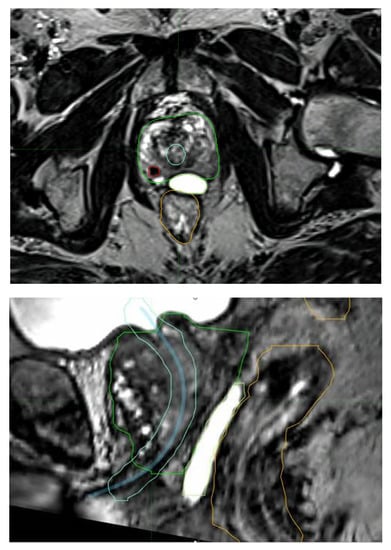

Due to its improved ability to accurately define the prostate and other relevant parts of the anatomy [67], MRI has helped substantially in safely delivering stereotactic radiotherapy. The PROMETHEUS trial with 135 patients employed MRI fusion for radiotherapy planning. MRI helps with delineation of all structures, including the DIL (Figure 4). This was a common feature in all of these vHDRB studies. Future studies can also be expected to utilize PSMA staging for both more accurate staging and DIL delineation.

Figure 4.

MRI fusion aiding with the identification of a dominant intraprostatic lesion (red), the urethra with expansion (blue and light blue), rectal sparing hydrogel (lime), the rectum (orange), and the prostrate (green).